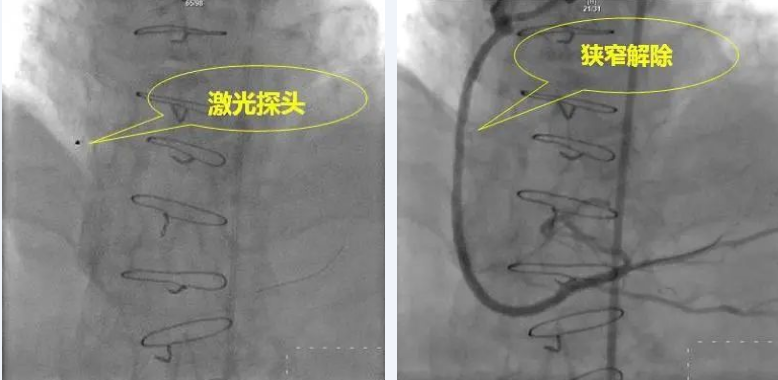

我院心内科李钢主任经过周密的考虑,在与家属充分沟通后,使用了目前国际上最先进的治疗技术——准分子激光冠状动脉成形术(ELCA技术),对狭窄部位进行消蚀,把原来堵塞支架的病变组织消蚀成微米级的、能够被自身免疫系统清除的颗粒,然后使用药物球囊在原来支架内壁上涂上了一层能够预防再狭窄的药物。

该技术采用波长为308nm的冷激光,通过光化学效应、光热效应和光机械效应三大效应达到治疗效果。即:通过发出高能量脉冲使病变组织内温度升高,组织汽化产生压力,通过迅速膨胀和收缩导致病变组织崩解,消蚀斑块物质,达到改善冠脉血流的效果。病变组织被消蚀成水、气体和微米级的微小物质,避免了血管内栓塞的发生,因而不易引起无复流及围术期心肌梗死等并发症。